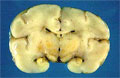

- (8)Kernicterus, nuclear icterus

Yellow discoloration of the brain parenchyma, most prominent in the basal ganglia and hippocampus (circle), is due to bilirubin accumulation associated with excess circulating bilirubin. The transition between postnatal/neonatal hemoglobin to hemoglobin A is often associated with jaundice caused by a transient increase in bilirubin which is in normal physiological ranges. However hemolytic disease of the new born (e.g. blood type incompatibility) may lead to excess bilirubin which in turn will results in accumulation of unconjugated bilirubin in the brain which can cause severe neurologic damage.